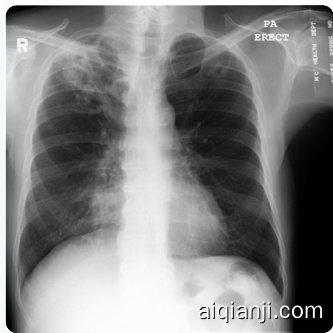

We also qualitatively explored the zero-shot chain-of-thought (CoT) capability of Med-PaLM M on the MC TB dataset. In contrast to the classification setup, we prompted the model with a text-only exemplar to generate a report describing the findings in a given image in addition to a yes/no classification prediction. In Figure 3, we present qualitative examples of zero-shot CoT reasoning from the Med-PaLM M 84B and 562B variants. In particular, both Med-PaLM M variants were able to identify the major TB related lesion in the correct location. However, according to expert radiologist review, there are still some omissions of findings and errors in the model generated report, suggesting room for improvement. It is noteworthy that Med-PaLM M 12B failed to generate a coherent visually conditioned response, which indicates that scaling of the language model plays a key role in the zero-shot CoT multimodal reasoning capability (i.e. this might be an emergent capability [13]).

我们还对Med-PaLM M在MC TB数据集上的零样本思维链(CoT)能力进行了定性探索。与分类设置不同,我们向模型提供了一个纯文本示例,要求其除了生成是/否分类预测外,还要生成描述给定图像中发现的报告。在图3中,我们展示了Med-PaLM M 84B和562B变体的零样本CoT推理定性示例。值得注意的是,两个Med-PaLM M变体都能在正确位置识别出与结核病相关的主要病变。然而,根据放射科专家评审,模型生成的报告中仍存在一些遗漏发现和错误,表明还有改进空间。需要指出的是,Med-PaLM M 12B未能生成连贯的视觉条件响应,这表明语言模型的规模在零样本CoT多模态推理能力中起着关键作用(即这可能是一种涌现能力[13])。

No. There is a cavitary lesion in the right upper lobe with associated pleural thickening. The left lung appears clear. The car dio media st in al silhouette is unremarkable.

不。右上肺有一个空洞性病变,伴有胸膜增厚。左肺清晰。心脏纵隔轮廓未见异常。

Correctness: There is a cavitary lesion in the right upper lobe with associated pleural thickening, which is the most important of multiple important TB-related findings on this image.

正确性:右上肺存在一个空洞性病变伴胸膜增厚,这是该影像中最重要的多项结核相关表现之一。

Incorrectness: The left lung is not clear, with a small cavitary lesion in the left upper lobe related to TB. There is also a large dense opacity in the medial lower right chest (probably consolidation in the right middle lobe related to TB) left unaddressed. This opacity partially obscures the right cardiac silhouette.

左肺显示不清,左上叶可见与结核相关的小空洞病变。右胸内侧下部还存在一处未处理的大片致密影(可能为右中叶与结核相关的实变),该致密影部分遮蔽了右心缘轮廓。

No. There is cavitary lesion in the right upper lobe. There is also right hilar and media st in al adenopathy. There is scarring in the right middle lobe. There is no pleural effusion.

右上肺叶存在空洞性病变。右肺门及纵隔淋巴结肿大。右肺中叶可见瘢痕形成。未见胸腔积液。

Correctness: There is a cavitary lesion in the right upper lobe, which is the most important of multiple important TB-related findings on this image. There is no pleural effusion.

正确性:右上肺存在一个空洞性病变,这是该影像中多个重要结核相关表现中最关键的一处。未见胸腔积液。

Figure 3 | Evidence of emergent zero-shot multimodal medical reasoning with Med-PaLM M. Large Med-PaLM M models exhibit zero-shot CoT reasoning capability in identifying and describing tuberculosis related findings in chest X-ray images. The model is prompted with task-specific instructions and a text-only exemplar (without the corresponding image) to generate a report describing findings in the given X-ray image. Model predictions from Med-PaLM M 84B and 562B are shown together with the annotations from an expert radiologist. Both models correctly localized the major TB related cavitory lesion in the right upper lobe. However, both models did not address the small cavitory lesion in left upper lobe (Med-PaLM M 562B was considered better than Med-PaLM M 64B in this example as it also alluded to the opacity in the right middle lobe and did not make the incorrect statement of left lung being clear). Notably, Med-PaLM M 12B failed to generate a coherent report, indicating the importance of scaling for zero-shot COT reasoning.

图 3 | Med-PaLM M 展现的零样本多模态医学推理能力。大型 Med-PaLM M 模型在识别和描述胸部 X 光片中肺结核相关表现时,展现出零样本思维链 (CoT) 推理能力。模型通过任务指令和纯文本示例(不含对应图像)生成描述给定 X 光片表现的报告。Med-PaLM M 84B 和 562B 的预测结果与放射科专家的标注共同展示。两个模型均准确定位了右肺上叶的主要结核性空洞病变,但都未提及左肺上叶的小空洞病变(此例中 Med-PaLM M 562B 表现优于 64B 版本,因其同时提示了右肺中叶的混浊表现,且未错误声明左肺无异常)。值得注意的是,Med-PaLM M 12B 未能生成连贯报告,这表明模型规模对零样本思维链推理至关重要。

Partial correctness: Scarring in the right middle lobe, and right hilar and inferior media st in al adenopathy may both allude to the large dense opacity in the medial lower right chest (probably consolidation in the right middle lobe related to TB).

部分正确:右肺中叶瘢痕形成,以及右肺门和下纵隔淋巴结肿大,均可能指向右下胸部内侧的大片致密影(可能为与结核相关的右肺中叶实变)。

Incorrectness: The small cavitary in the left upper lobe lesion related to TB is unaddressed.

左上肺叶结核相关的小空洞病变未得到处理。